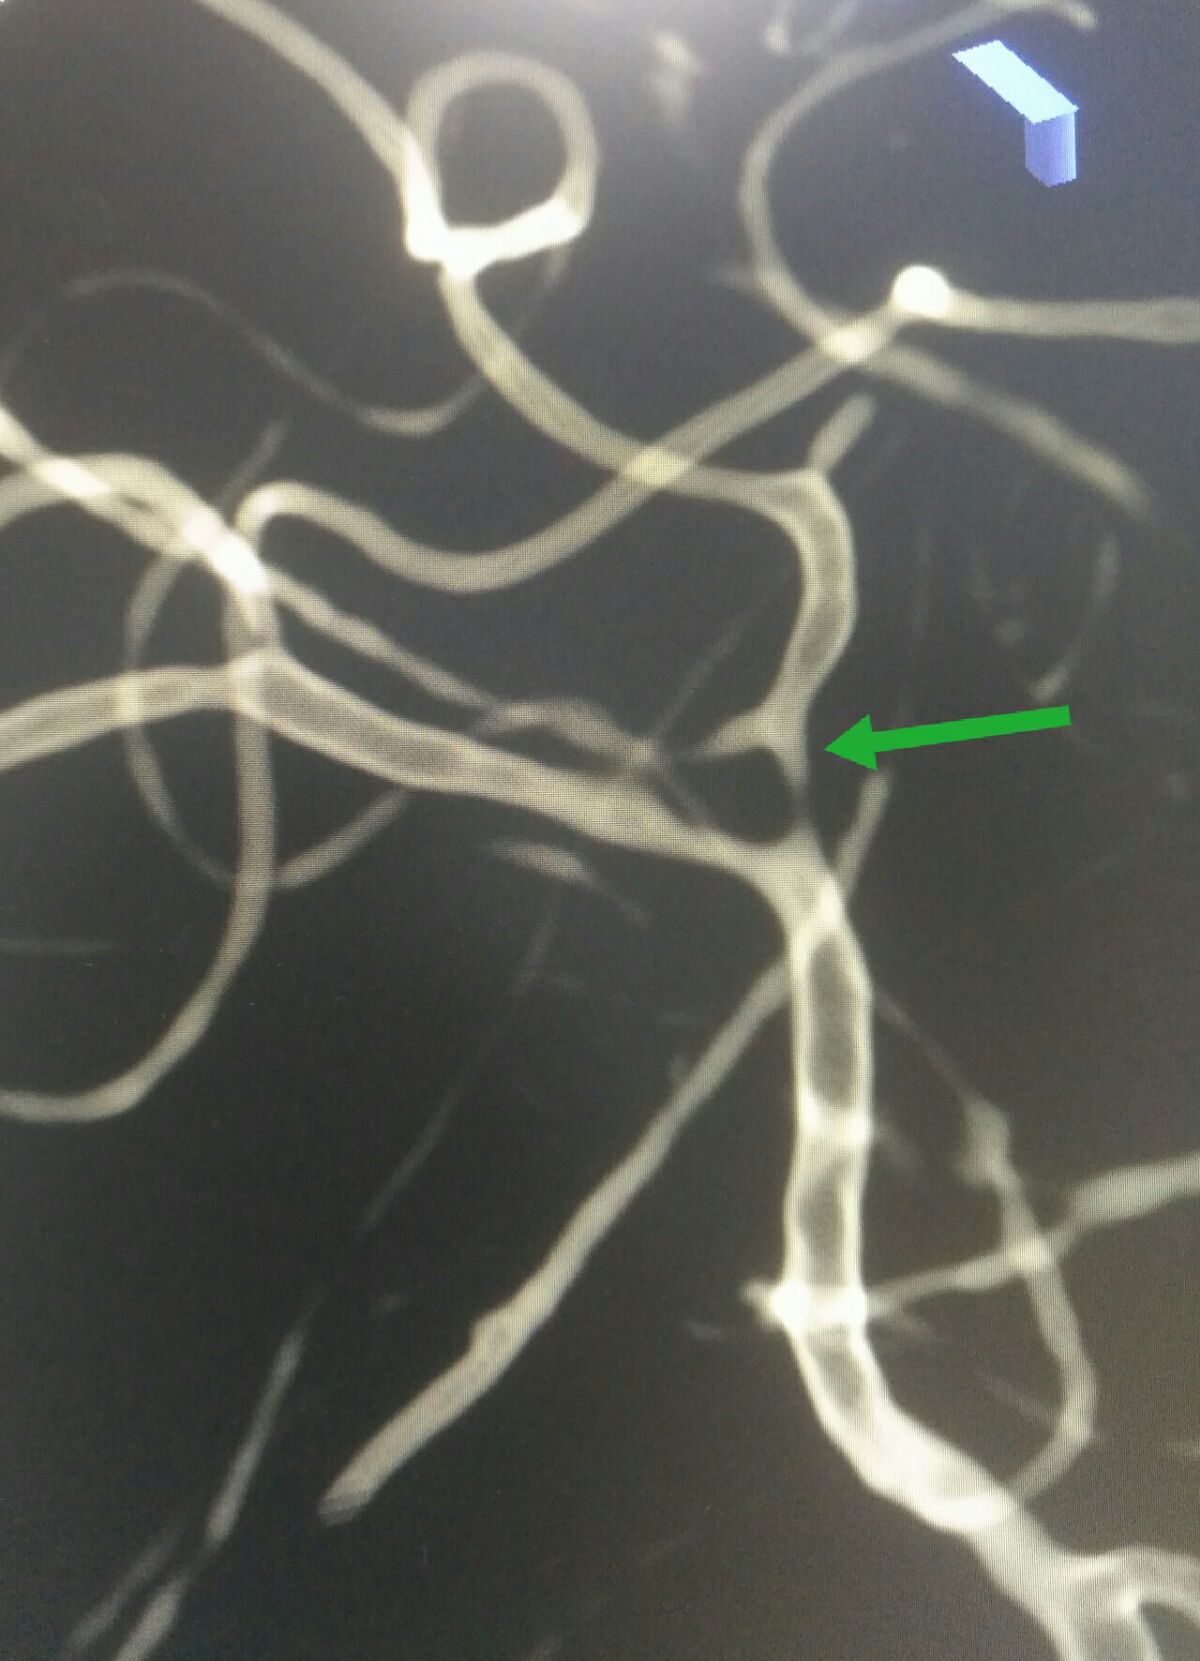

3D处理后可见大脑中动脉下干重度狭窄

3D处理后可见大脑中动脉下干重度狭窄

3D处理后不同角度显示大脑中动脉下干重度狭窄